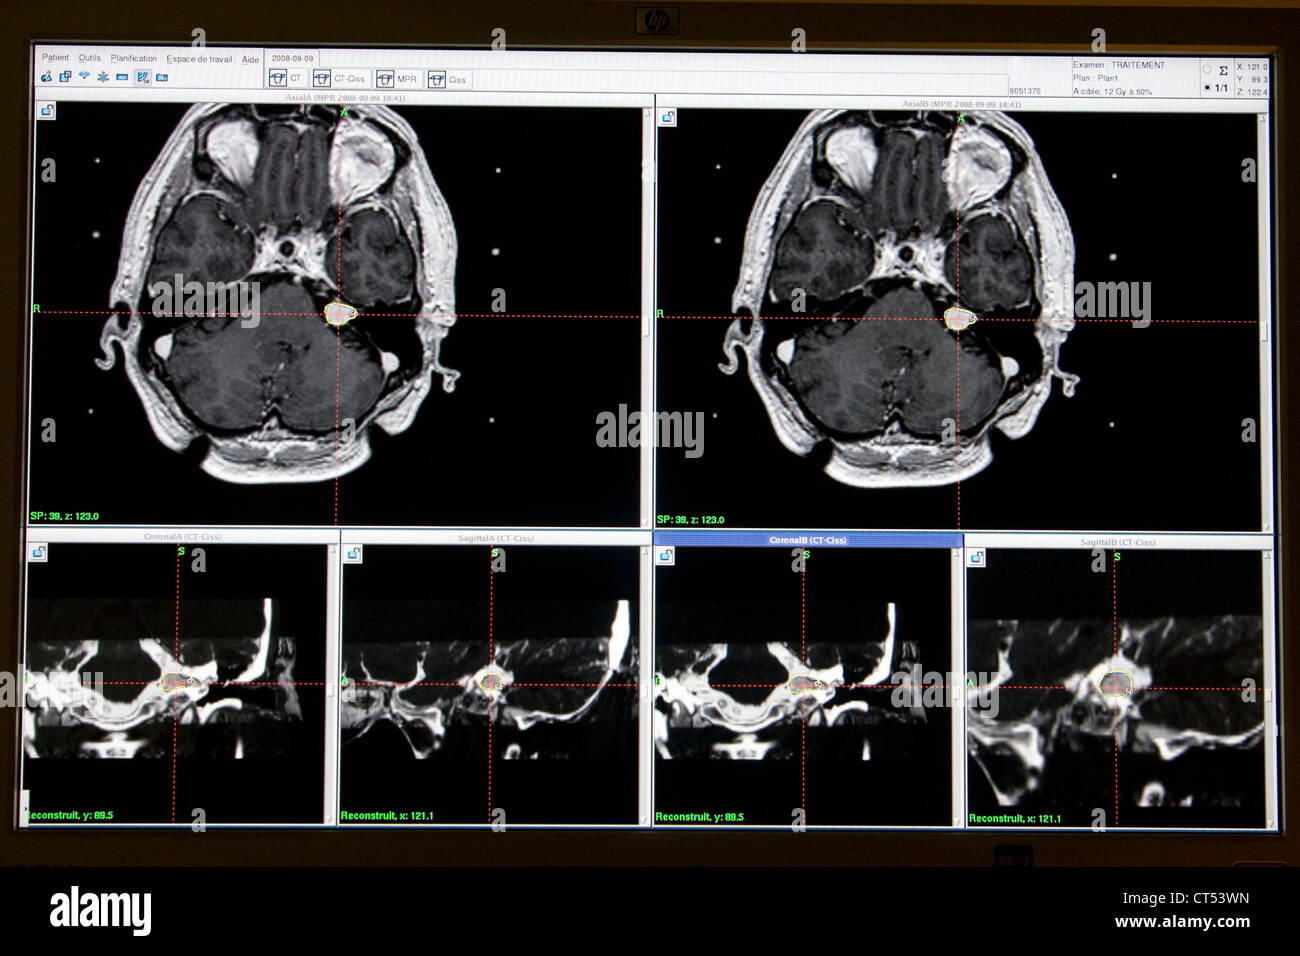

neurinome de l'acoustique schwannome vestibulaire from www.neurochirurgie-lariboisiere.com

neurinome de l'acoustique schwannome vestibulaire

Acoustic neuroma hires stock photography and images Alamy. Découvrez des témoignages poignants sur le neurinome de l'acoustique, une tumeur rare touchant le nerf auditif Actuellement l'équipe de neurochirurgie et celle de radiochirurgie doivent se réunir pour décider de ce qui peut être réalisé pour me soigner : chirgurgie ou radiochirurgie